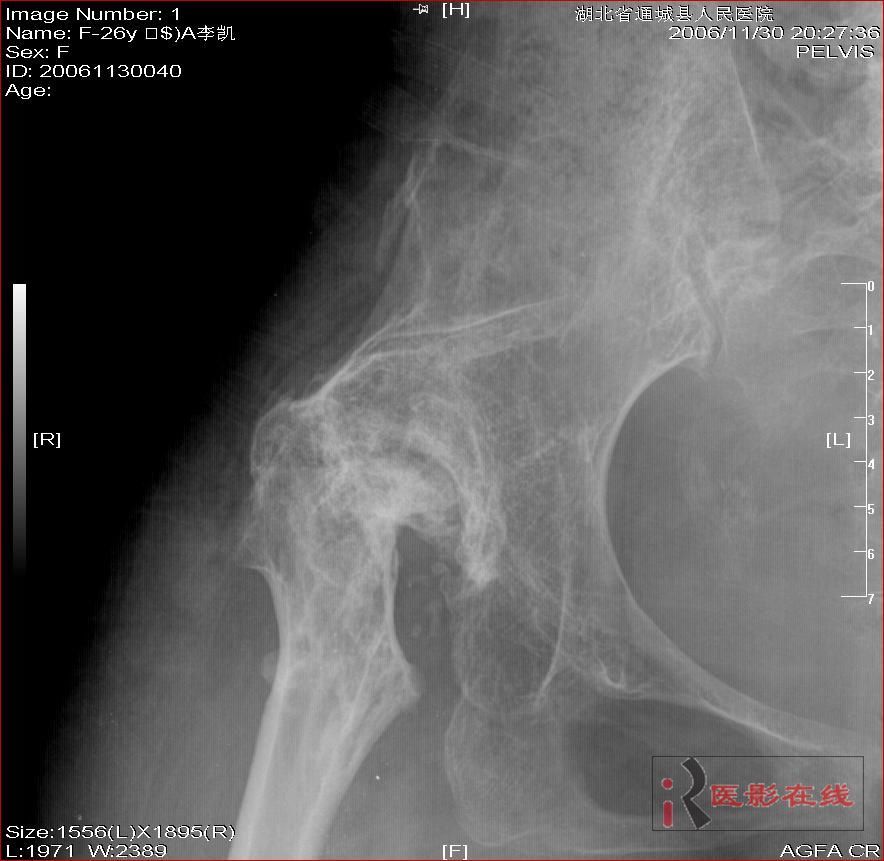

先天性双髋关节脱位自体骨关节再造

女 28岁 先天性髋关节脱位术后复查片(手术日期是2000年,数字化以前平片资料患者外带),现无其它不适,走路仍需双拐

2006年11月30日

1右髋形成假关节.

2双髋骨质退变.

3无菌坏死可能.

双侧髋关节仍为脱位表现,假关节形成,部分已经强直,右股骨头碎裂,股骨干近端增粗。

结合手术史考虑:原地臼盖成形术后,髋关节退变,股骨头无菌性坏死,右股骨近端生长紊乱,骨质疏松。